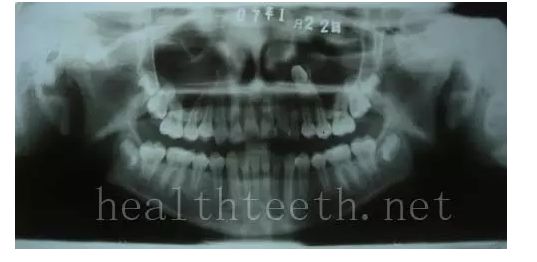

左上乳3滯留,恒3未見萌出,曲面斷層片顯示牙齒埋伏